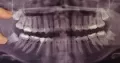

Мне 19 лет. Сильно искривились зубы за последние полтора года. Проконсультировался с ортодонтами в платных клиниках для установки систем брекетов, сказали удалять все восьмерки, удалил верхние и сейчас предстоит удаление нижних, засевших в челюсть. Но на фоне боязни возникает вопрос в надобности:

Все верно, для ортодонтического лечения необходимо создание места в зубном ряду, путем удаления зубов мудрости. Без данной манипуляции ничего не получится, а скученность будет только увеличиваться, а также страдают соседние седьмые зубы. У вас далеко не самое сложное удаление и не стоит так переживать, эти зубы вы в любом случае удалите. Вам необходимо обратиться к грамотному и опытному хирургу, во избежании негативных последствий. Запишитесь на очный прием к хирургу.